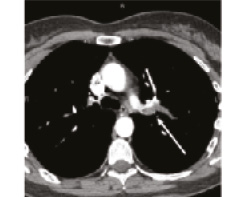

В 1993 г. на основании характерных признаков электрокардиограммы (ЭКГ) при профилактическом обследовании диагностирован феномен Вольфа–Паркинсона–Уайта. Клинических проявлений, снижающих качество жизни, пациентка не отмечала. К врачам далее не обращалась. В связи с появлением в 2015 г. одышки, перебоев в работе сердца, сердцебиения наблюдалась у участкового терапевта с диагнозом: ишемическая болезнь сердца, гипертоническая болезнь. Эхокардиография (ЭхоКГ), нагрузочные тесты не проводились. На фоне приема лозартана 25 мг/сут достигнуты целевые значения АД. В январе 2017 г. в связи с зарегистрированным на ЭКГ пароксизмом тахикардии с узкими комплексами QRS пациентка в порядке скорой помощи поступила с диагнозом «пароксизмальная суправентрикулярная тахикардия» в ЦРБ, где ритм был медикаментозно восстановлен. Далее в краевой больнице проведено внутрисердечное электрофизиологическое исследование и по его результатам – радиочастотная аблация дополнительных проводящих путей. Послеоперационный период протекал без осложнений. Однако в июне 2017 г. вновь появилась одышка при выполнении привычного объема физической нагрузки. По данным ЭКГ и рентгенограммы органов грудной клетки патологии не выявлено. Вскоре появилось кровохарканье (в течение 3 дней), и пациентка была направлена к фтизиатру, которым исключен туберкулез легких. 27.07.2017 на фоне значительного усиления одышки, выраженной тахикардии она потеряла сознание и в порядке скорой помощи доставлена в дежурный стационар, где травматологом и неврологом исключены сотрясение головного мозга и закрытая черепно-мозговая травма. Пациентка отпущена домой. В связи с сохраняющейся одышкой при подъеме на один лестничный пролет в августе 2017 г. по собственной инициативе она обратилась к кардиологу. При проведении ЭхоКГ выявлены увеличение правых камер сердца и признаки их объемной перегрузки. С предварительным диагнозом ТЭЛА пациентка направлена в дежурный стационар, где в экстренном порядке проведена спиральная компьютерная томография (СКТ) с контрастированием легочной артерии. Выявлены признаки легочной тромбоэмболии крупных и средних ветвей легочной артерии (ЛА) с обеих сторон (рис. 1–4). При целенаправленном сборе анамнеза выяснилось, что в течение 3 лет (с 2014 г.) пациентка принимает Линдинет 20 мг – монофазный пероральный контрацептив (этинилэстрадиол + гестоден), назначенный гинекологом с целью контрацепции. По данным ультразвукового исследования вен нижних конечностей выявлен тромбоз суральных вен справа. Линдинет отменен. На фоне лечения антикоагулянтами (гепарин, эноксапарин) состояние женщины несколько улучшилось. Она переведена на варфарин, который далее заменен на апиксабан в дозе 10 мг 2 раза в день.

СКТ с контрастированием ЛА | |

14.08.2018 | 26.09.2018 |

Рис. 3: а – тромбы в нижнедолевой ветви левой ЛА и нижнедолевой ветви правой ЛА; б – сохраняется тромбоз нижнедолевой ветви правой ЛА. | |

Рис. 4: а – тромбы в левой ЛА и ее ветвях; б – тромбоза левой ЛА (нисходящей ветви) не выявлено, сохраняется тромбоз нижнедолевой ветви левой ЛА. | |